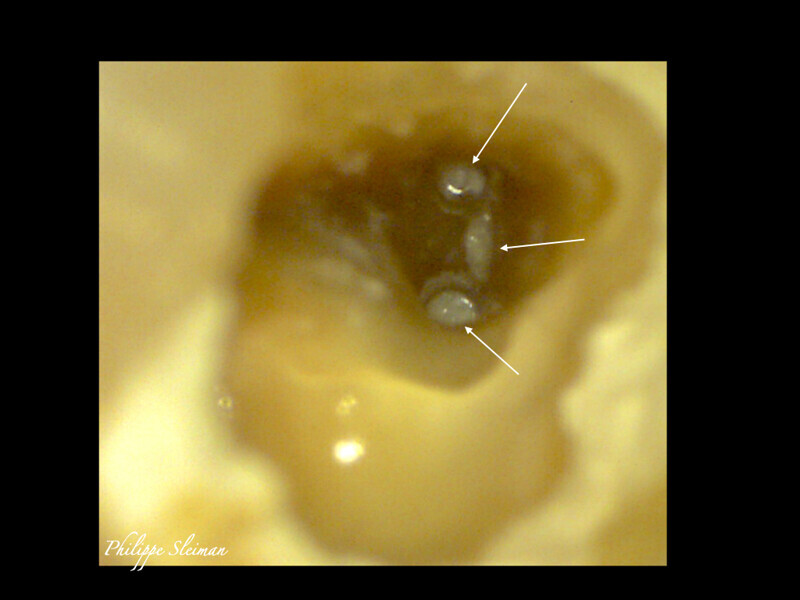

Clinical management of maxillary second molar root canal therapy in different anatomical situations